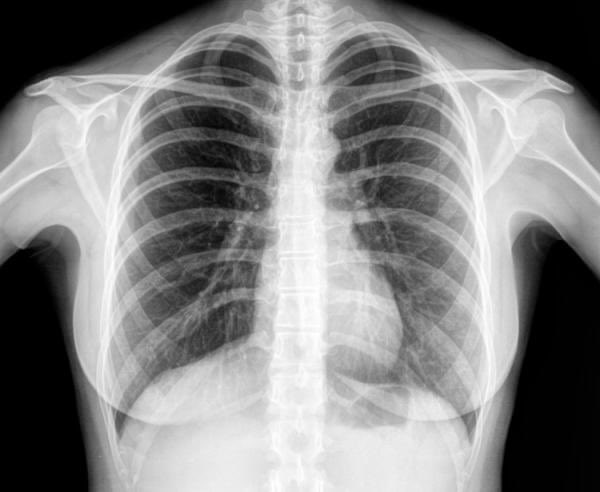

2) متلازمة الصدر الحاد(Acute chest syndrome)